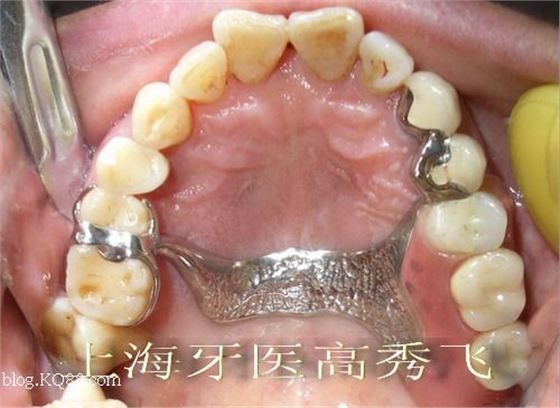

修復(fù)設(shè)計(jì):13、14為附著體基牙,烤瓷冠修復(fù),遠(yuǎn)中放置三段可調(diào)式附著體,考慮到對側(cè)牙齒無齲壞,設(shè)計(jì)25、26雙臂卡,上頜后腭板鈷鉻合金支架義齒。牙齒制備后合面觀:

附著體戴入后合面觀: